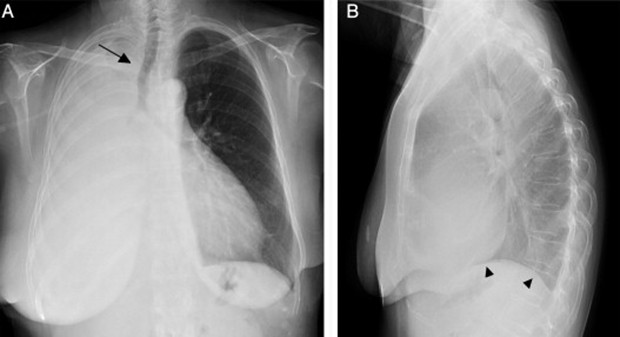

Paciente masculino de 23 años quien es llevado a consulta por productiva, malestar general fatiga y

disnea. Menciona además que últimamente ha tenido que utilizar más veces al día

su tratamiento de rescate para asma. Entre los antecedentes menciona que cree

que la Pachamama es perfecta, así que se come todas las verduras tal cual las

recoge de la siembra sin lavarla ni hervirla. Además, menciona tener malestar

abdominal, dolores tipo cólico, náuseas, meteorismo, vómitos ocasionales y

diarrea. Se le realiza un examen de heces que menciona que tiene

"huevos" y una biopsia pulmonar que verán a continuación... Con base

a toda la información... ¿Cuál de las siguientes radiografías torácicas es más

probable que tenga este paciente?